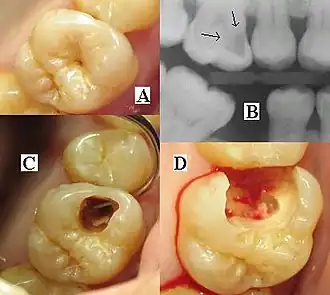

| Destruction of a tooth by dental caries and disease | |

Tooth decay, also known as caries,[a] is the breakdown of teeth due to acids produced by bacteria.[6] The resulting cavities may be many different colors, from yellow to black.[1] Symptoms may include pain and difficulty eating.[1][2] Complications may include inflammation of the tissue around the tooth, tooth loss and infection or abscess formation.[1][3] Tooth regeneration is an ongoing stem cell–based field of study that aims to find methods to reverse the effects of decay; current methods are based on easing symptoms.

The presentation of caries is highly variable. However, the risk factors and stages of development are similar. Initially, it may appear as a small chalky area (smooth surface caries), which may eventually develop into a large cavitation. Sometimes caries may be directly visible. However, other methods of detection, such as X-rays, are used for less visible areas of teeth and to judge the extent of destruction. Lasers for detecting caries allow detection without ionizing radiation and are now used for the detection of interproximal decay (between the teeth).

Primary diagnosis involves inspection of all visible tooth surfaces using a good light source, dental mirror, and explorer. Dental radiographs (X-rays) may show dental caries before it is otherwise visible, in particular caries between the teeth. Large areas of dental caries are often apparent to the naked eye, but smaller lesions can be difficult to identify. Visual and tactile inspection, along with radiographs, are employed frequently among dentists, in particular to diagnose pit and fissure caries.[89] Early, uncavitated caries is often diagnosed by blowing air across the suspect surface, which removes moisture and changes the optical properties of the unmineralized enamel.

At times, pit and fissure caries may be difficult to detect. Bacteria can penetrate the enamel to reach dentin, but then the outer surface may remineralize, especially if fluoride is present.[91] These caries, sometimes referred to as "hidden caries", will still be visible on X-ray radiographs, but visual examination of the tooth would show the enamel intact or minimally perforated.